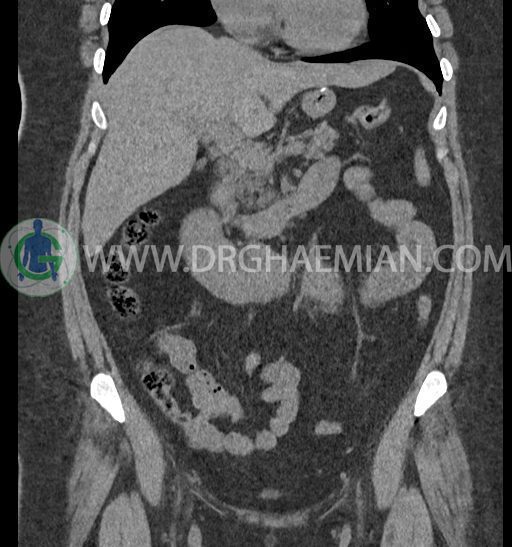

سی تی اسکن شکم و لگن با استفاده از اشعات ایکس تصاویر عرضی از ناحیه شکم و لگن ایجاد میکند. در این کیس کلیه نعل اسبی و سنگ کلیه مشاهده می شود.

در سی تی اسکن اسپیرال شکم و لگن بدون کنتراست (مولتی دیدکتور 16 با مقاطع ظریف و بازسازی های ساژیتال و کرونال) :

-شواهد جراحی اسلیو قبلی در Body و فوندوس معده

-آپاندیس نرمال بصورت رتروسکال

مشهود است.